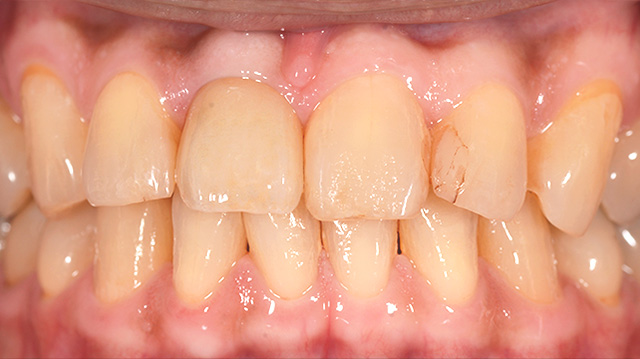

| 年代・性別 | 50代 男性 |

|---|---|

| 主訴 | インプラントをしたいが他の歯医者では難しいからと断られた |

| 治療期間 | 約1年 |

| 費用 |

仮歯 5,500円 ジルコニアクラウン 176,000円 インプラント 300,000円 インプラント仮歯 22,000円 サージカルガイド 70,000円 |